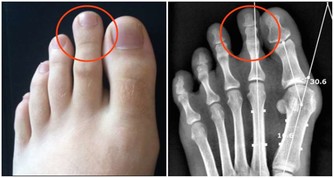

不想被痛風盯上,少吃2種食物,改掉1個壞習慣,自然啥事也沒有

所謂內源性尿酸,是人體代謝過程中自行產生的。當體內嘌呤代謝紊亂,或惡性腫瘤等疾病患者因放化療使腫瘤細胞大量破壞分解,也會導致血尿酸水平的急劇上升。

1.少食高嘌呤食物

如動物內臟、海鮮、火鍋、啤酒等。